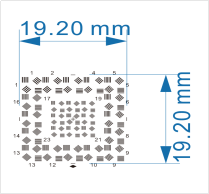

| FDA認證-畸變 | 點陣圖 |  | FDA認證 | 測試畸變 | |

| 棋盤格 |  | FDA認證 | 測試畸變 | ||